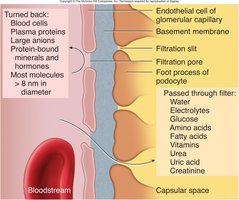

Filtration Membrane

The filtration membrane consists of three layers: fenestrated endothelium, basement membrane, and podocyte filtration slits. It allows passage of water, ions, glucose, amino acids, and small proteins, but restricts blood cells and large proteins.

Filtration: Passive movement of fluid and solutes from blood into the nephron.

Renal Corpuscle: Includes the glomerulus (fenestrated capillary bed) and Bowman’s capsule (with podocytes forming filtration slits).

Filtration in the glomerulus is driven by hydrostatic and osmotic pressures. The net filtration pressure (NFP) determines the amount of filtrate produced.

HPgc: Hydrostatic pressure in glomerular capillaries (forces fluid out).

HPcs: Hydrostatic pressure in capsular space (opposes filtration).

OPgc: Osmotic pressure of plasma proteins (draws fluid back in).